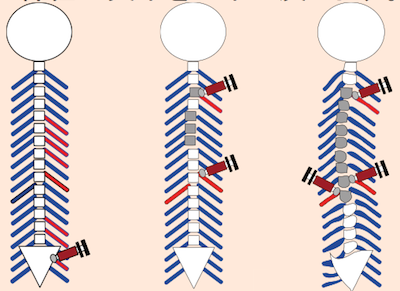

アクティベータ・メソッドで神経のバランスを整える

施術では、アクティベータ・メソッドを用いて神経関節機能(サブラクセーション)のバランスを整えました。 この方法は、「骨を矯正する」というよりも、 神経が正常に働ける環境を整えることを目的としています。

けんこうカイロプラクティックセンターの施術は、「腰痛を治すこと」よりも、「腰痛が治る身体をつくること」を目的としています。そのため、腰痛のお客さまであっても、首や全身の神経バランスを整えるケアを行います。 身体全体の神経の流れをスムーズにすることで、イネイトインテリジェンス(自然治癒力)が最大限に発揮されます。 ⸻椎間板ヘルニア・坐骨神経痛でお悩みの方へ